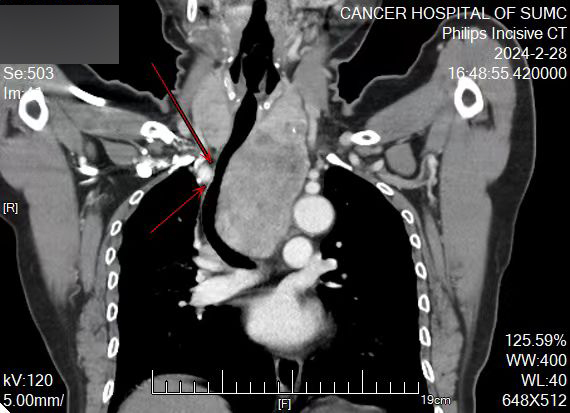

手术前,根据许阿姨的病情,麻醉科进行了全科术前疑难病例讨论,根据放射科陈俊伟医生的三维重建图像,大家反复探讨各种可行方案、存在风险及应急预案,最后制定了“保留自主呼吸清醒气管插管”的方案。

巨大胸骨后甲状腺肿三维重建图像,气管受压变形弯曲狭窄